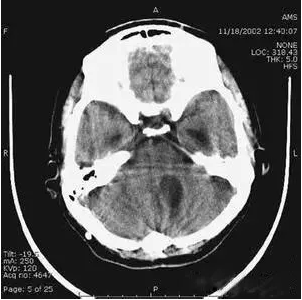

6、部分容積效應產生的偽影及對策

部分容積效應偽影的形狀可因物體的不同而不一樣,一般在重建后橫斷面圖像上可見條形、環形或大片干擾的偽像。最常見和典型的現象是在頭顱橫斷面時的顳部出現的條狀偽影,又稱哼氏偽影。該偽影現象可采用薄層掃描而減弱;在西門子系列的CT機中.用VAR掃描技術可抑制該偽影。